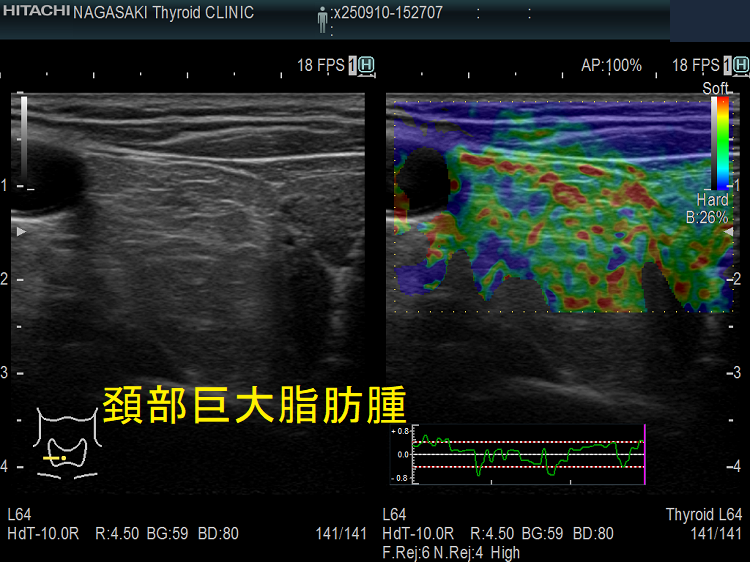

巨大頚部脂肪腫

血管脂肪腫は脂肪腫の一種で脂肪と血管を含みます。20歳から30歳までの若年成人に発症し、その原因として、

ほとんどが前腕ですが、頚部に現れる場合もあります。痛みを伴う点が脂肪腫と異なり、脂肪肉腫とも鑑別を要します。[Skeletal Radiol. 2023 Mar;52(3):541-552.]